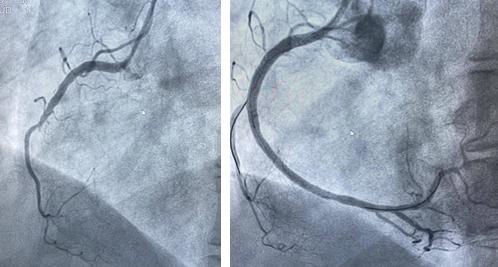

情况紧急,胸痛中心迅速响应,在与家属沟通并签署知情同意书的同时,同步办理住院手续,全程开通绿色通道,以最快的速度把吕女士送入导管室接受急诊PCI治疗(经皮冠状动脉介入治疗)。在王宁夫主任医师指导下,徐鹏和钱宇峰副主任医师为她进行介入治疗,术中发现她的右侧冠状动脉近段完全闭塞,通过球囊扩张并植入支架,成功开通了堵塞的血管,恢复了心肌供血。